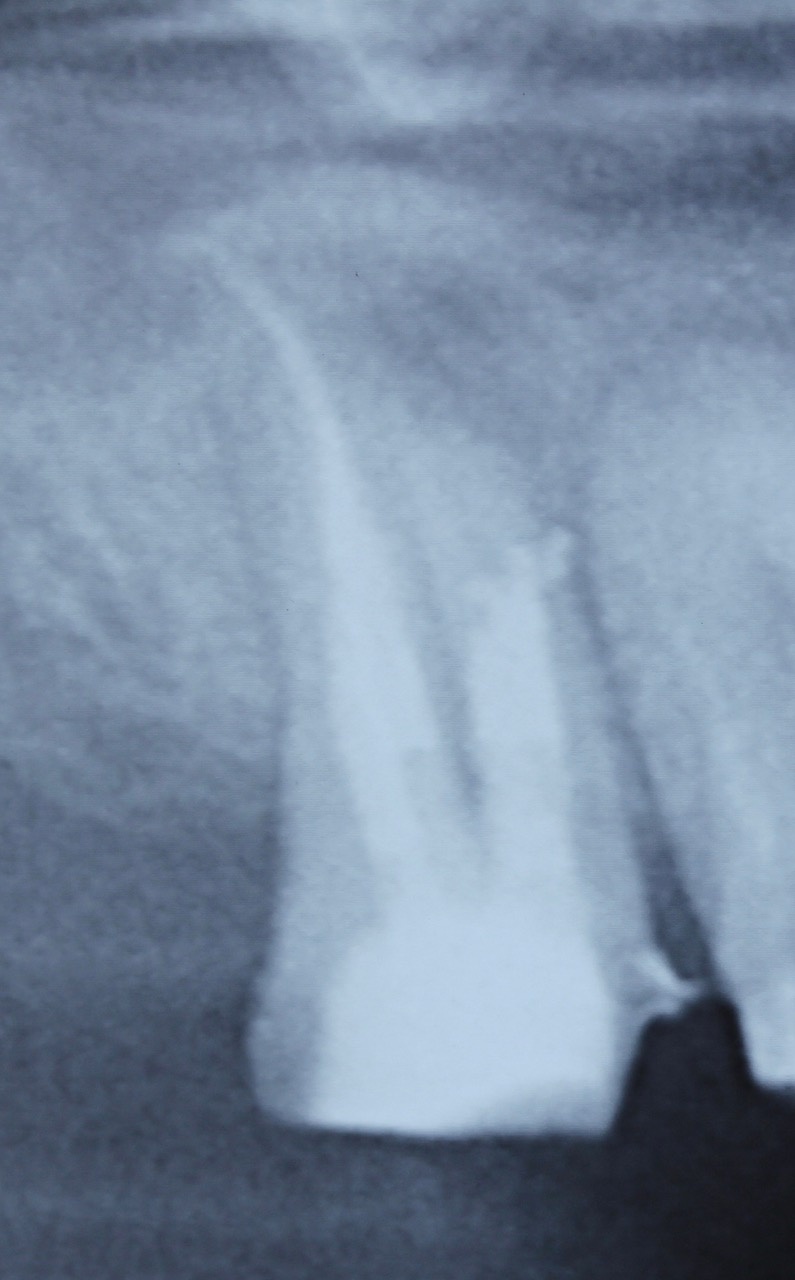

Im ersten Fall stellte sich die Patientin nach bereits erfolgter endodontischer Behandlung an Zahn 47 mit Beschwerden, die insbesondere bei okklusaler Belastung auftraten, vor. Die Provokation mittels Perkussion fiel positiv aus. Das daraufhin angefertigte Röntgenbild (Abb. 1) zeigte eine bis zum Apex reichende Wurzelfüllung mit apikaler Aufhellung und Ausdehnung der Osteolyse bis zum Dach des Nervus alveolaris inferior. Insgesamt war die Wurzelfüllung als inhomogen zu bewerten. Nach Aufklärung über die Therapiealternativen entschied sich die Patientin für einen Revisionsversuch.

Ein nach Applikation des MTA angefertigtes Kontrollbild zeigt den suffizienten apikalen Verschluss der Konstriktion in einer Schichtstärke von etwa vier Millimeter (Abb. 2). Gleichzeitig wird in der Aufnahme die ausgedehnte Kanalstruktur des Zahnes 47 deutlich.